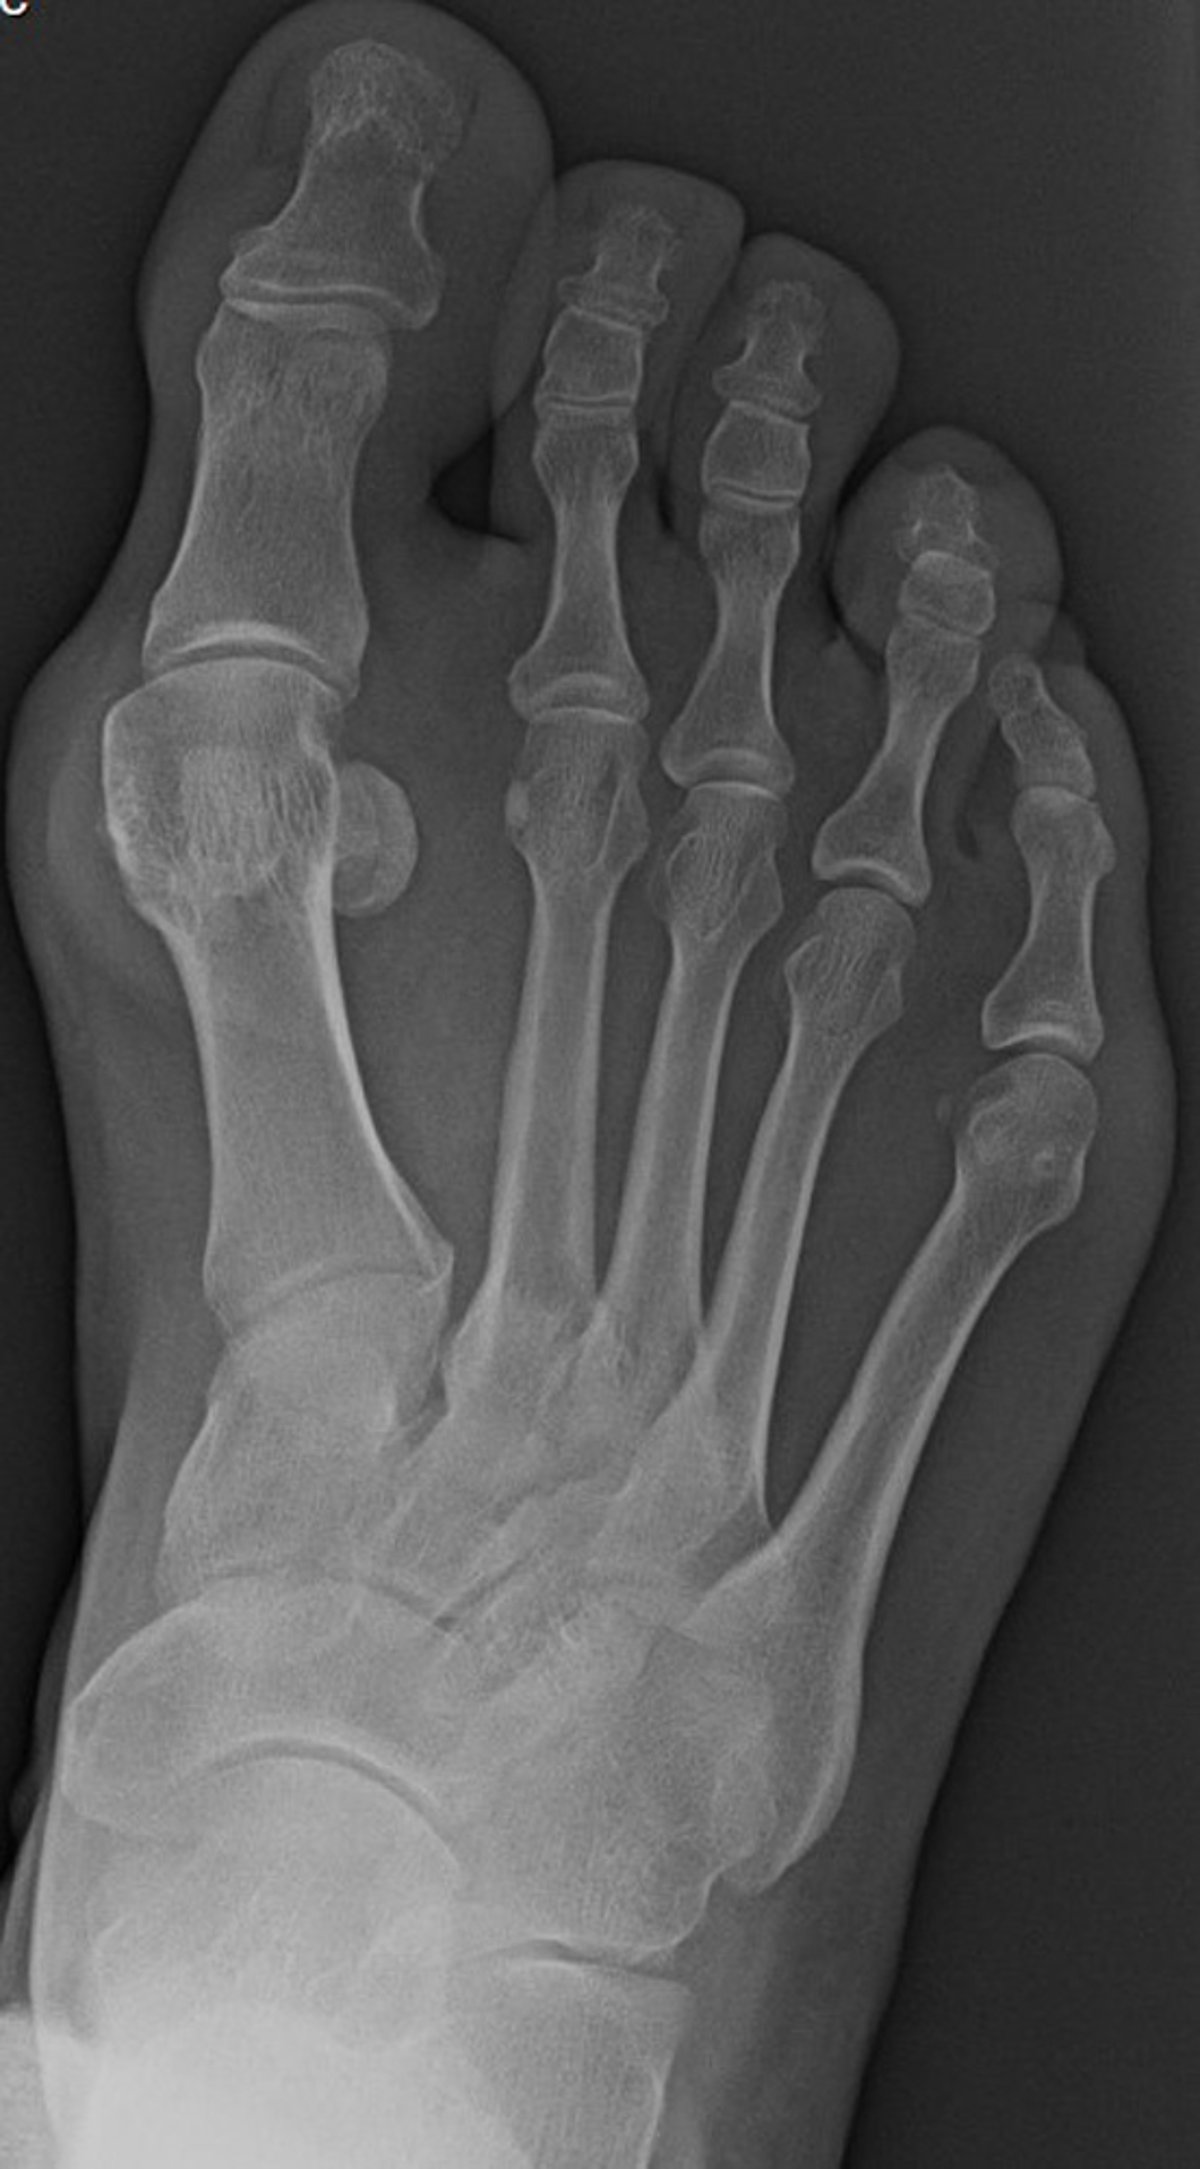

Переднезадняя рентгенограмма стопы с бурситом

На этой переднезадней проекции стопы показаны рентгенографические данные, соответствующие вальгусной деформации, с медиальным отклонением первой плюсневой кости. Наблюдается также латеральный подвывих основания первой проксимальной фаланги по отношению к головке первой плюсневой кости.

Image courtesy of James C. Connors, DPM.